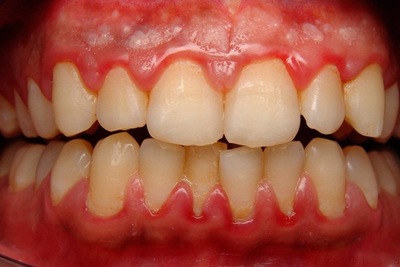

Язвенный гингивит

Воспаление тканей десны, вместе с которым происходит эрозия, изъязвление и некроз десневого края.

Фото 1. Язвенный гингивит обычно причиняет пациентам резкую болезненность десны на фоне имеющегося воспаления.

Симптомы воспаления:

- резкая боль, затрудняющая приём еды;

- наличие неприятного запаха изо рта;

- отёк, кровоточивость дёсен;

- образование на дёснах язв;

- повышенная температура тела;

- общее недомогание.

Важно! Чаще всего язвенный гингивит образуется у людей 18 – 30 лет. Как правило, протекает остро, но при определённых условиях может перейти в подострую или хроническую форму, в язвенный стоматит и пародонтит.